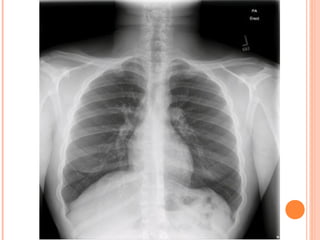

• #9 The typical features of asthma are well-depicted on this chest radiograph of an adolescent with persistent asthma. In the AP view, peribronchial thickening is evident as is evidence of hyperinflation of the lungs. What if we noted on this X-ray that the heart was on the right side, would that change our differential? Primary ciliary dyskinesia AKA Cartaginer’s

• #10 Hyperinflation is often best seen on the lateral chest radiograph with flattening of the diaphragms and expansion of the retrocardiac air space.